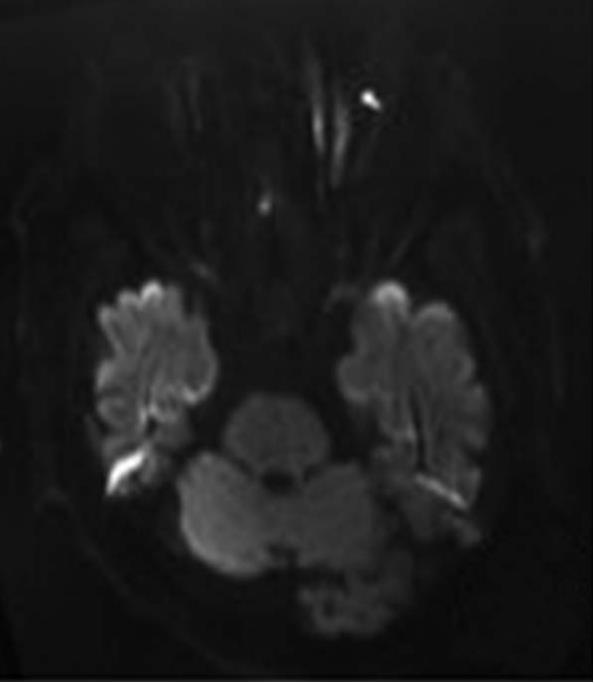

3.治疗概要 入院后完善相关检查,考虑超早期缺血性脑卒中。给予rt-PA替普酶静脉溶栓,24h后予抗血小板聚集等治疗,但效果欠佳,行头颅MRI+DWI显示双侧基底节区、双侧大脑半球白质多发腔隙性梗死,DWI序列未见急性梗死;脑白质稀疏、脑萎缩(图5-2)。入院第12天,左侧肢体肌力4级。追问患者有颈部疼痛史,否认有外伤史。遂行颈椎MRI平扫提示颈椎退行性变,C2/3、C3/4、C4/5、C5/6椎间盘突出,颈椎骨质增生;C3/4椎管狭窄,脊髓水肿,C3/4椎间盘层面脊髓损伤(图5-3)。于2016年5月21日至手术室行全麻气管插管下颈椎后路椎板切除+神经探查+侧块螺钉内固定急诊手术(图5-4),术中发现C3/4椎间盘突出。术后给予积极脱水、神经营养、激素冲击、改善循环等治疗后病情痊愈。

6.辅助检查:头颅CT未见明确梗死及出血灶(图5-1)。头颅MRI+DWI显示双侧基底节区、双侧大脑半球白质多发腔隙性梗死,DWI序列未见急性梗死;脑白质稀疏、脑萎缩;全副鼻窦炎,双侧下鼻甲肥大;双侧乳突窦炎。颈椎MRI平扫提示颈椎退行性变,C2/3、C3/4、C4/5、C5/6椎间盘突出,颈椎骨质增生;C3/4椎管狭窄,脊髓水肿,C3/4椎间盘层面脊髓损伤。

2.定性诊断 患者急性起病,结合患者有颈部疼痛病史,溶栓后治疗效果不佳,颅脑MRI未见急性梗死,颈椎MRI示颈椎退行性变,C2/3、C3/4、C4/5、C5/6椎间盘突出;C3/4椎管狭窄,脊髓水肿,C3/4椎间盘层面脊髓损伤,定性诊断为颈椎椎间盘突出并颈椎管狭窄。

图5-3 颈椎MRI示C2/3、C3/4、C4/5、C5/6椎间盘突出,C3/4椎管狭窄,脊髓水肿,C3/4椎间盘层面脊髓损伤